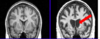

State where this stroke has occured

Right MCA